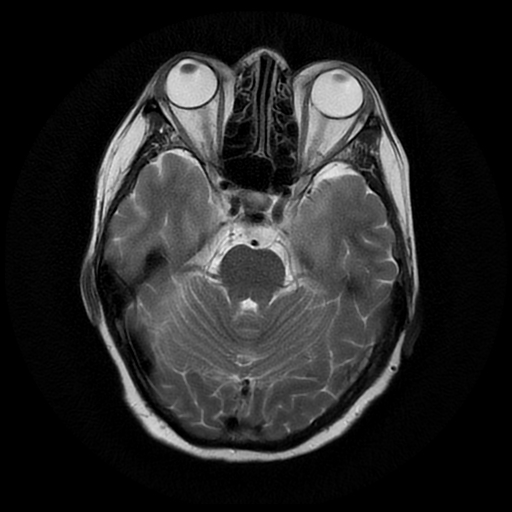

Lateral and Medial Ankle Ligaments

Lateral Ligaments

Deltoid Ligament Complex

Deep Components (2)

1. ATTL -- attached to anterior colliculus of MM - thin

2. PTTL -- attached to posterior colliculus of MM (fan shaped, striated(cf AITFL), lower 2/3's often bright)

Superficial Components (3)

1. TNavL

2. TSpringL - most important - coronal plane best

3. TCalcL

All blend with Superomedial component of Spring Ligament

Spring (Calcaneonavicular) Ligament

3 Components:

1. Superomedial CNL - most important -- abN if >5mm

2. Medioplantar oblique

3. Inferopalntar longitudinal - as thick as little finger

Periosteal apposition -- new periosteal bone superficial to cortex. Sign of chronic injury. Best on axial. With or without ossicles